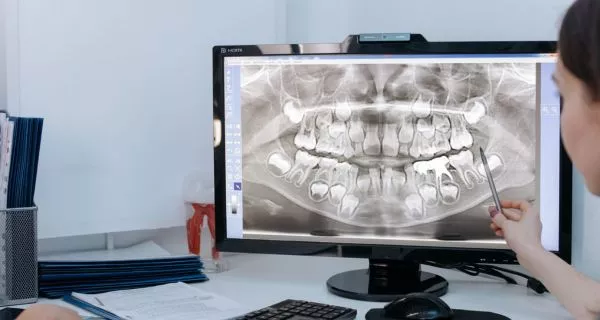

Dental X-rays help us see what we cannot see with our eyes. They help find cavities, infections, impacted teeth, or jaw problems. At Channel Islands Family Dental Office in Ventura County, we use periapical X-rays and panoramic X-rays, depending on the needs of each patient. We always follow safety rules and use very low radiation.

A panoramic X-ray gives a full image of your mouth. It shows all your teeth, your jaw, the joints, and your sinuses. It is not as detailed as a periapical X-ray, but it gives a big-picture view that is very useful for many treatments.